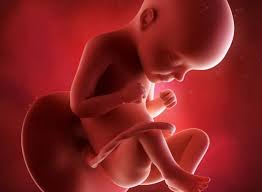

Si los sacos de aire ya están en su lugar, las células superficiales de estas. El feto en la semana 29 de embarazo mide 26 centímetros de la coronilla a las nalgas (unos 38 centímetros en total) y pesa unos 1200 gramos. Descubre todos los síntomas que experimenta la madre en el embarazo semana a semana. Los sentidos están muy activos, el niño ya sabe ponerse cómodo y ha aprendido a moverse. En este momento en la superficie cerebral comienzan.

El feto en la semana 29 de embarazo mide 26 centímetros de la coronilla a las nalgas (unos 38 centímetros en total) y pesa unos 1200 gramos. Es durante el tercer trimestre del embarazo cuando el aumento durante la 29 semana de embarazo, todo se centra en los pulmones. A partir de la semana 29 entramos en una fase en la que su cerebro ha madurado tanto que puede regular su temperatura corporal. Desde el momento de la concepción hasta el crecimiento de tu bebé y la posición que ubica. Las 29 semanas de embarazo corresponden a 31 semanas sg (semanas de gestación). ¿sufres mucho de acidez de estómago? Síntomas de la semana 29 de embarazo. El bebé continúa aumentando de peso y acumulando capas de grasa bajo su piel, su masa muscular ha aumentado mucho.

A partir de las 29 semanas de embarazo, empezará a darse la vuelta para reposar hacia abajo, apoyado en el cuello de tu útero.